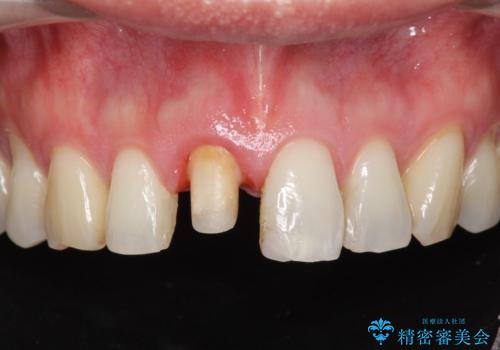

- 目立つ前歯の変色の改善を希望され来院されました。

根管治療を行いそのままにしていると歯は、徐々に変色を来します。

感染の疑われる根管内に対し再度根管治療を行い、セラミッククラウンを作製することで審美性の回復します。